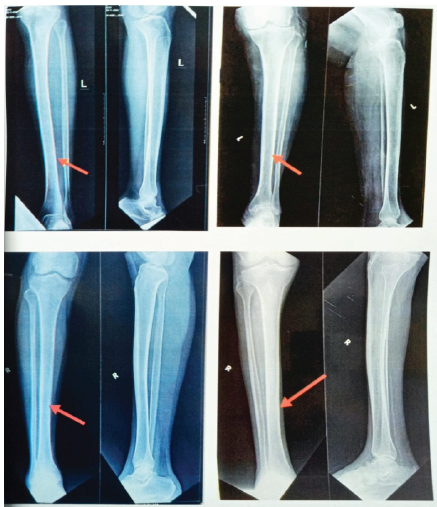

The data were entered into MS Excel (Windows) and further analyzed using SPSS software (version 20; SPSS Inc., Chicago IL, USA). For descriptive analysis, the categorical variables were analyzed using frequency and percentages; the continuous variables were analyzed by calculating mean ± standard deviation. For inferential analysis, the continuous (ordinal) data were analyzed using Independent “t” test/ Mann–Whitney test, and the categorical data were analyzed using Chi-square test and “P < 0.05” will be considered as statistically significant. The mean age of the participants in the fibula fixed group was 45 years, whereas it was 37 years in the fibula not fixed group. The tibial bone union was clinically better in the fibula not fixed group (100%) when compared with the fibula fixed group (70.6% of cases), i.e.,12 out of 17 patients. Thus, the study was found to have statistically significant association between the tibia union and fibula fixation (P = 0.032*) (Fig. 4). RUST score whose mean was 9.47 in fibula fixed and 10.92 among fibula not fixed group showed significant difference between the two groups (P = 0.047*) based on the results of non-parametric Mann–Whitney test (Fig. 5). (Among 29% of fibula fixed cases with tibial non union, (i.e., 5 cases), the fixation implant for tibia used was plate in 4 cases and IM nail in 1 case). The coronal and sagittal plane alignment were maintained within normal range in both groups and occurrence of post-operative infection was similar in both groups and they were statistically insignificant. Tibial torsion was typically absent in all patients, hence was constant. Table 1 shows the summary of the study results of 30 patients.

Figure 4: Illustrates union and non-union of fracture among cases and controls.

Figure 5: Comparison of radiographic union score for tibial fractures scoring between Group A and Group B.